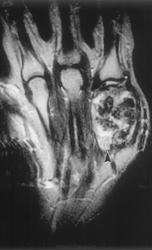

Гигантоклеточная опухоль.

Злокачественная гигантоклеточная  опухоль возникает из доброкачественной (частота 10-20%). После операции возможно появление рецидива опухоли.